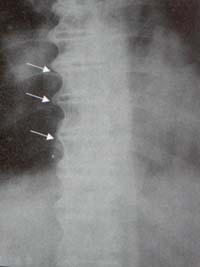

En la columna torácica el desorden comienza en la región media o inferior. Particularmente en casos tempranos una zona radiolúcida se nota entre el depósito óseo y la vértebra subyacente. Estas áreas radiolúcidas dentro de la masa osificada son comunes a nivel del disco intervertebral y corresponden a la extensión anterolateral del material discal. La formación ósea es más prominente a lo largo del lado derecho de la columna torácica inferior, presumiblemente debido a la inhibición de la osificación del lado izquierdo por la pulsación de la aorta (Figura 14)10.

Figura 14. Columna Dorso-lumbar. Se aprecian osteofitos marginales a lo largo del lado derecho de la columna torácica, formando puentes óseos, en un paciente con DISH (Flechas).